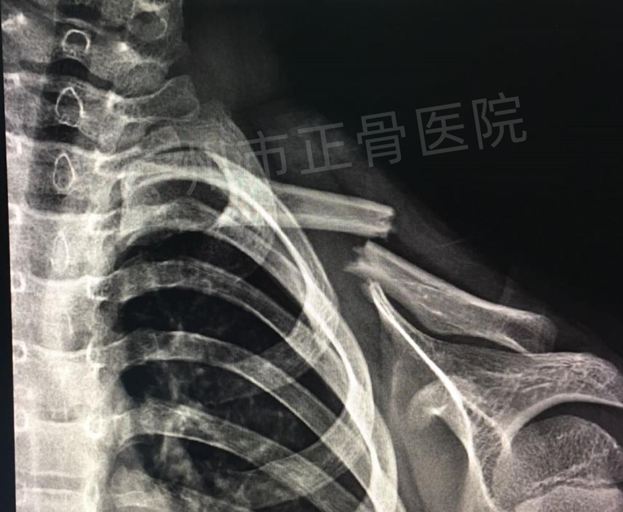

X线检查:左锁骨中段骨折,骨折近端向前上方移位,骨折远端向后下方移位。

▲复位前,骨折端移位